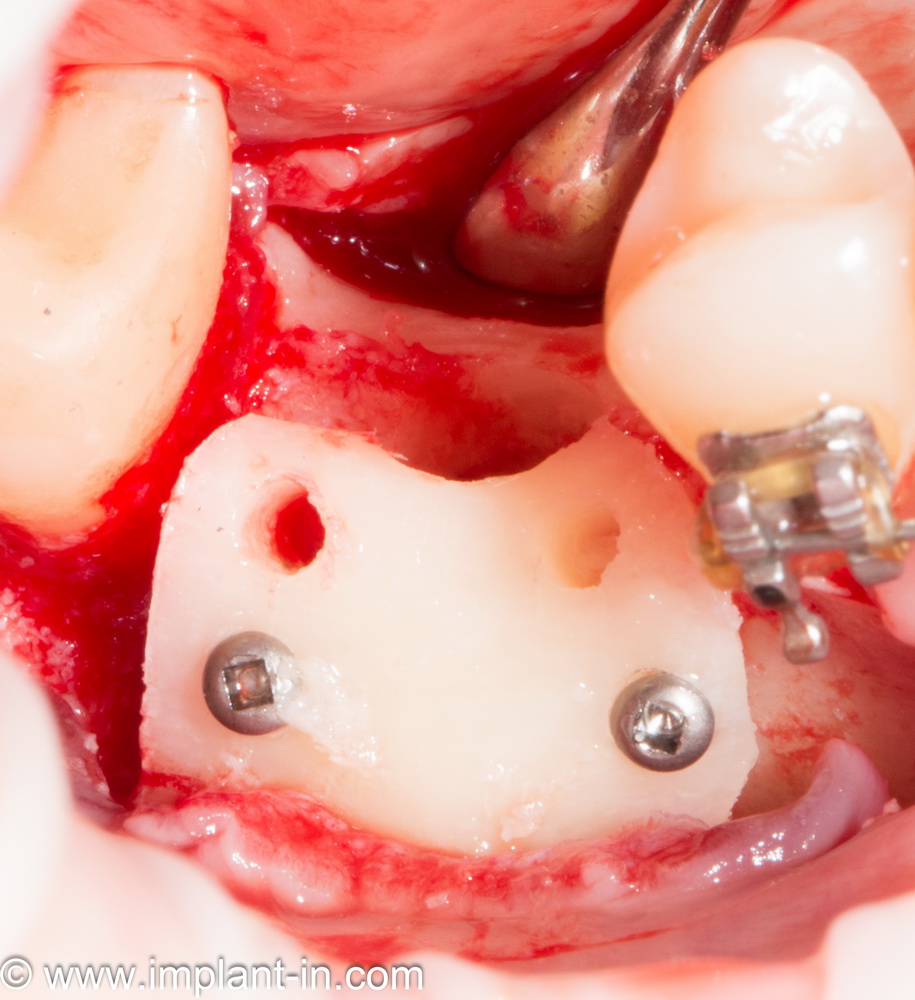

Остеопластические операции: факторы успеха